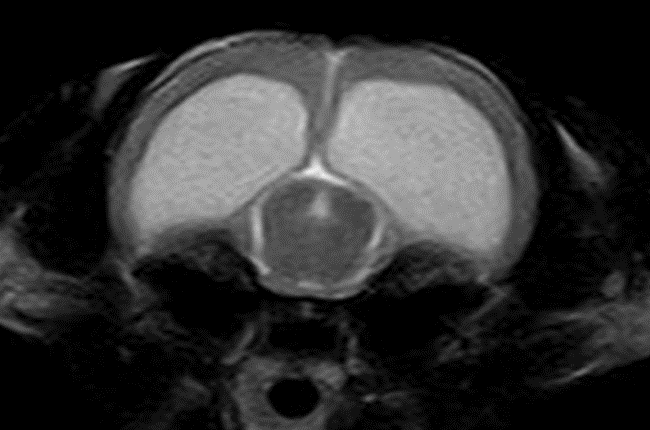

◈ 水頭症

MR画像(T2WI)

MR画像(T2WI)